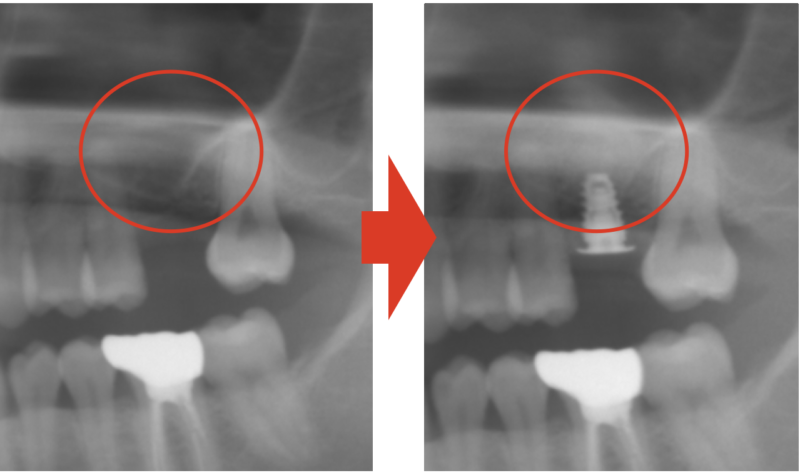

術前術後比較

当院ではこのように、上顎の骨造成も問題なく行えます。